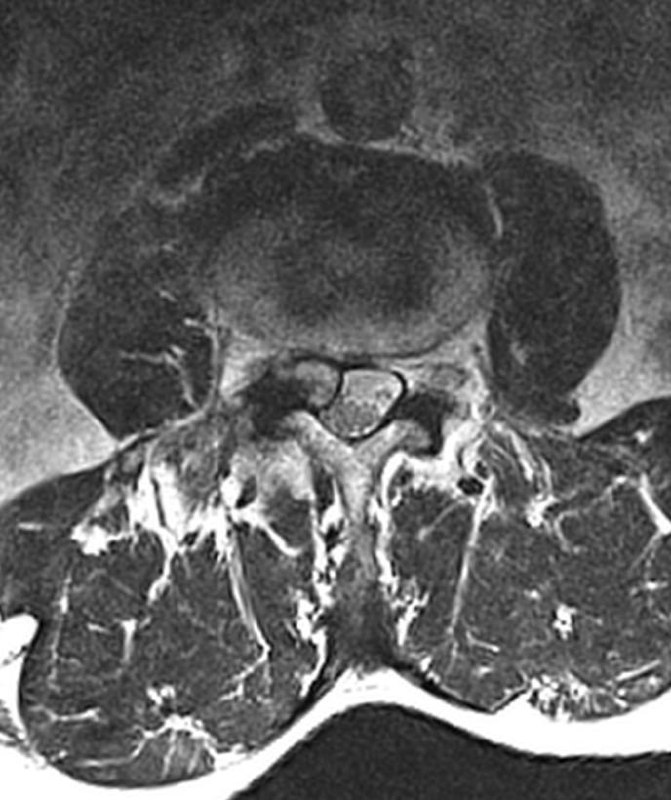

Когда рак простаты видно вот так, как здесь - исследование не вызывает отвращения, в отличие от случаев, когда приходится писать PIRADS-3..

Другое дело, что мы ж о пациентах заботимся, а не о себе, любимых, и каждый PIRADS-3 для пациента, все же, лучше, чем легко и непринуждённо обнаруживаемый, как в данном случае, PIRADS-5.

Пожелаем этому мужчине 75 лет успехов в лечении и минимума неприятных ощущений, которыми, неизбежно, такое лечение сопровождается.